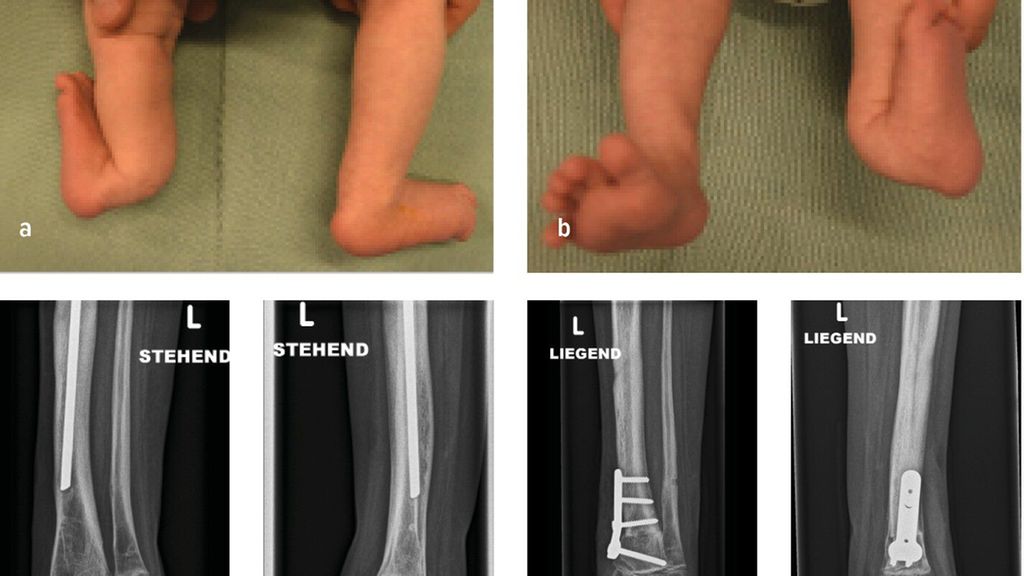

Abb. 1: 6-Jähriger mit unilateraler FH und 4-strahligem Fuß rechts sowie ausgeprägter Beinlängendifferenz vor chirurgischer Rekonstruktion (a–c). Laufende Valguskorrektur und Beinlängenausgleich mittels externen hexapoden Fixateurs mit Fußeinschluss

Die neuere Unterteilung nach Paley bezieht die Sprunggelenkspathologien in die Klassifikation mit ein (vier Typen mit Untergruppen) und gibt auch hier Empfehlung zu operativen Verfahren ab.1 Ziele der chirurgischen Rekonstruktion umfassen die Fußkorrektur mit plantigrader Position, den Ausgleich der Beinlängendifferenz bei Wachstumsabschluss sowie eine neutrale Beinachse. Neben konservativen Maßnahmen wie Schuhzurichtungen und Orthosenversorgung, erfolgt die Korrektur schließlich über chirurgische Verfahren wie Stabilisierungstechniken des Knie- und Sprunggelenkes, Wachstumslenkung sowie beinverlängernde Maßnahmen. Im Fall des 6-jährigen Patienten erfolgten eine Valguskorrektur und ein Beinlängenausgleich mittels externen hexapoden Fixateurs und Fußeinschluss (Abb.1d,e).6 In besonders schweren Fällen mit ausgeprägter Fehlbildung und Hypoplasie des Fußes kann eine Amputation mit anschließender Orthoprothesenversorgung in Betracht gezogen werden.7

Abb. 3: 6 Wochen altes Mädchen mit posteromedialem Bowing der linken unteren Extremität (a+b) sowie postoperative Bildgebung

Verbleibende Fehlstellungen, insbesondere Rekurvation der Tibia, Beinlängendifferenz, Torsionsfehler oder Valgusfehlstellung der Tibia oder des Sprunggelenkes, bedürfen einer chirurgischen Intervention. Die dysplastische keilförmige Wachstumsfuge an der distalen Tibia begünstigt in einigen Fällen die Valgusfehlstellung im Sprunggelenk. Im Rahmen der Bildgebung präsentiert sich in dieser Abbildung ein 6 Jahre altes Mädchen mit einer selten auftretenden verbleibenden Valgusfehlstellung im Sprunggelenk bedingt durch eine dysplastische keilförmige Wachstumsfuge bei Z.n. Korrektur und Verlängerung mittels Fixateur externe und Stabilisierung mit intramedullärem Nagel (Abb.3c,d). Als chirurgische Therapien stehen hierfür die Wachstumslenkung an der distalen Tibia oder akute (supramalleoläre Korrekturosteotomien (Abb.3e,f) bzw. graduelle (externer Fixateur) Korrekturen zur Verfügung. Verbleibende Beinlängendifferenzen können durch eine Wachstumsbremsung der kontralateralen Seite bei geringer Beinlängendifferenz oder mittels gradueller Distraktionsosteogenese (externer Fixateur) therapiert werden.14,16,17